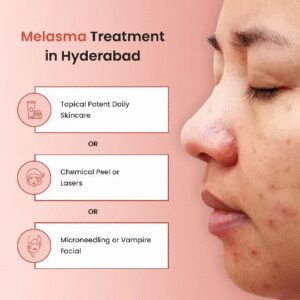

Melasma is a common skin condition that causes brown or gray-brown patches, typically on the […]